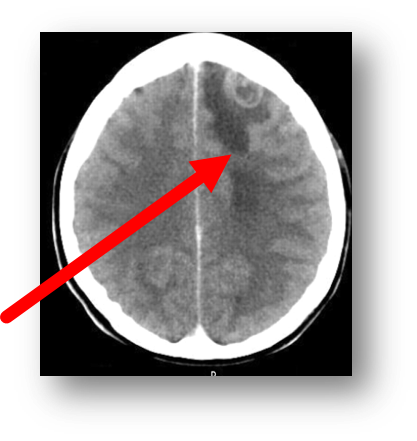

Q

metastatic lesion